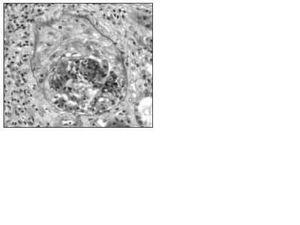

Biopsia Renal: Glomerulonefritis proliferativa difusa mesangial y endocapilar (11% de esclerosis glomerular, 22% de semilunas epiteliales, aumento difuso de la celularidad mesangial y endotelial, infiltrado inflamatorio crónico en el intersticio. Inmunofluorescencia: depósitos granulares en las membranas basales y mesangio de C3, IgG e IgA, C4, C1q.) (fig. 1).

Figura 1.